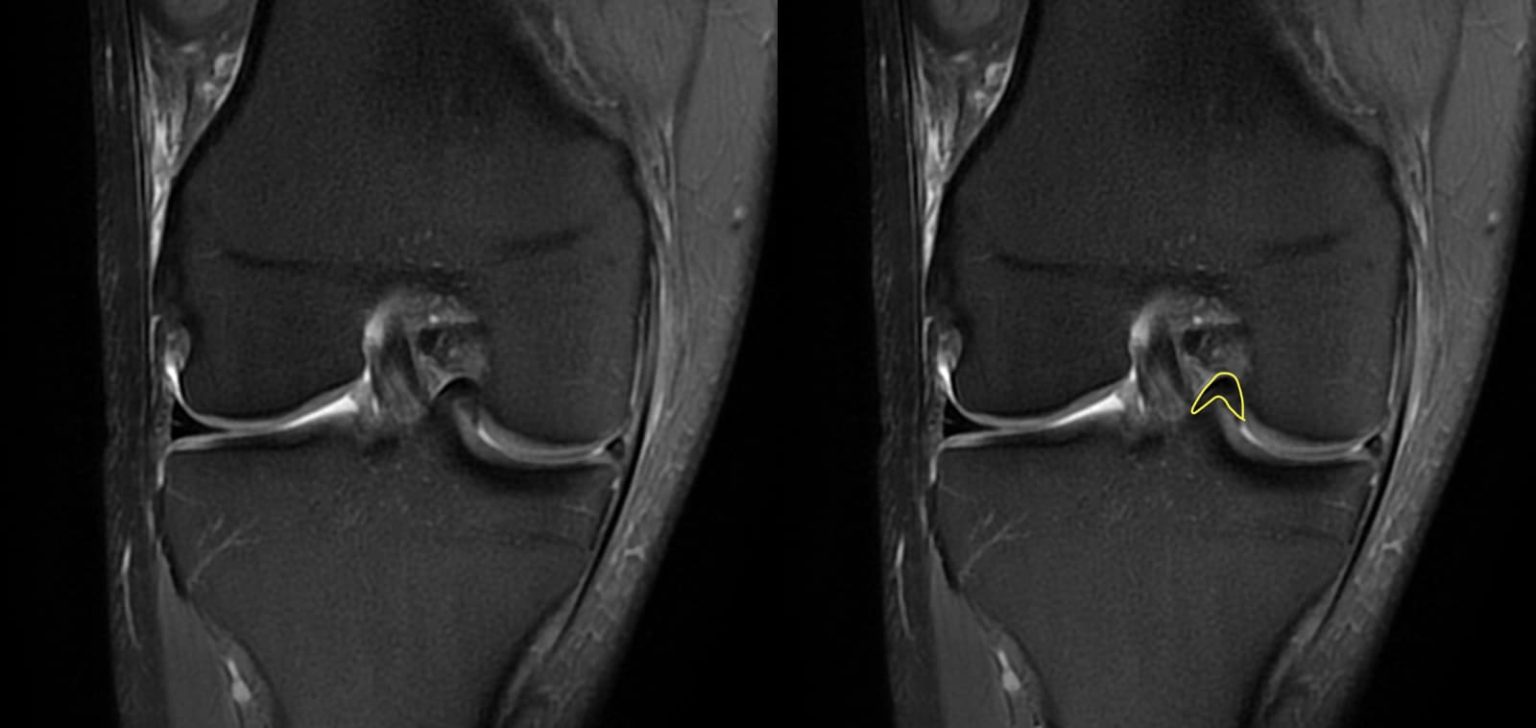

Chirurgie des ménisques Chirurgie Orthopédique Nice Dr Arnaud Clavé. La durée de convalescence d'un ménisque fissuré dépendra de plusieurs facteurs, tels que la gravité de la fissure, le type de traitement mis en place et la condition physique du patient Il est important de noter que chaque cas de fissure du ménisque est unique et doit être évalué individuellement par un professionnel de la santé

méniscectomie et suture méniscale par arthroscopie Docteur Matthieu Meyer. Les déchirures partielles sont les plus courantes et peuvent être causées par un mouvement brusque du genou, une torsion excessive ou une usure progressive due au vieillissement. Afin de vous accompagner dans votre convalescence après l'opération d'un ménisque fissuré, vous devrez effectuer des séances de kinésithérapie